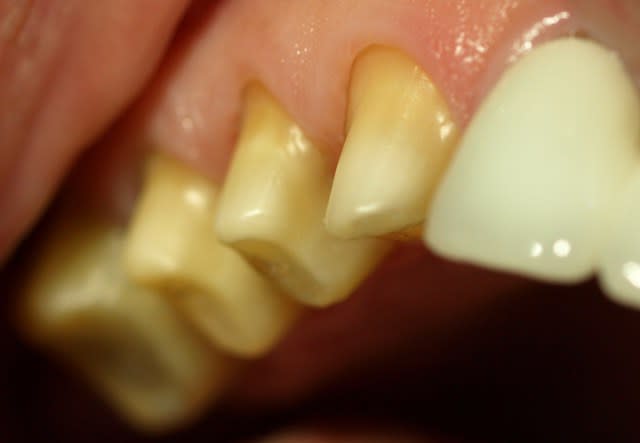

tient un boulot ou il y a un peu de tout.

bridge antérieur , car la pose d'implants nécessitait de la reconstruction trop importante, endo couronne sur les molaires mandibulaires par manque de hauteur, onlay. implants à la mandibule.

A noter les 2 PM maxillaires qui comportaient

chacune 3 canaux.